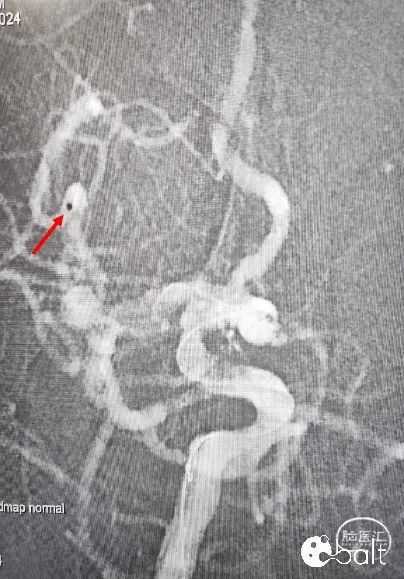

术后影像

术后工作位手推造影、术后正位造影。

术后工作位手推造影

术后正位造影

术后造影显示动脉瘤致密栓塞,各分支血管血流通畅。